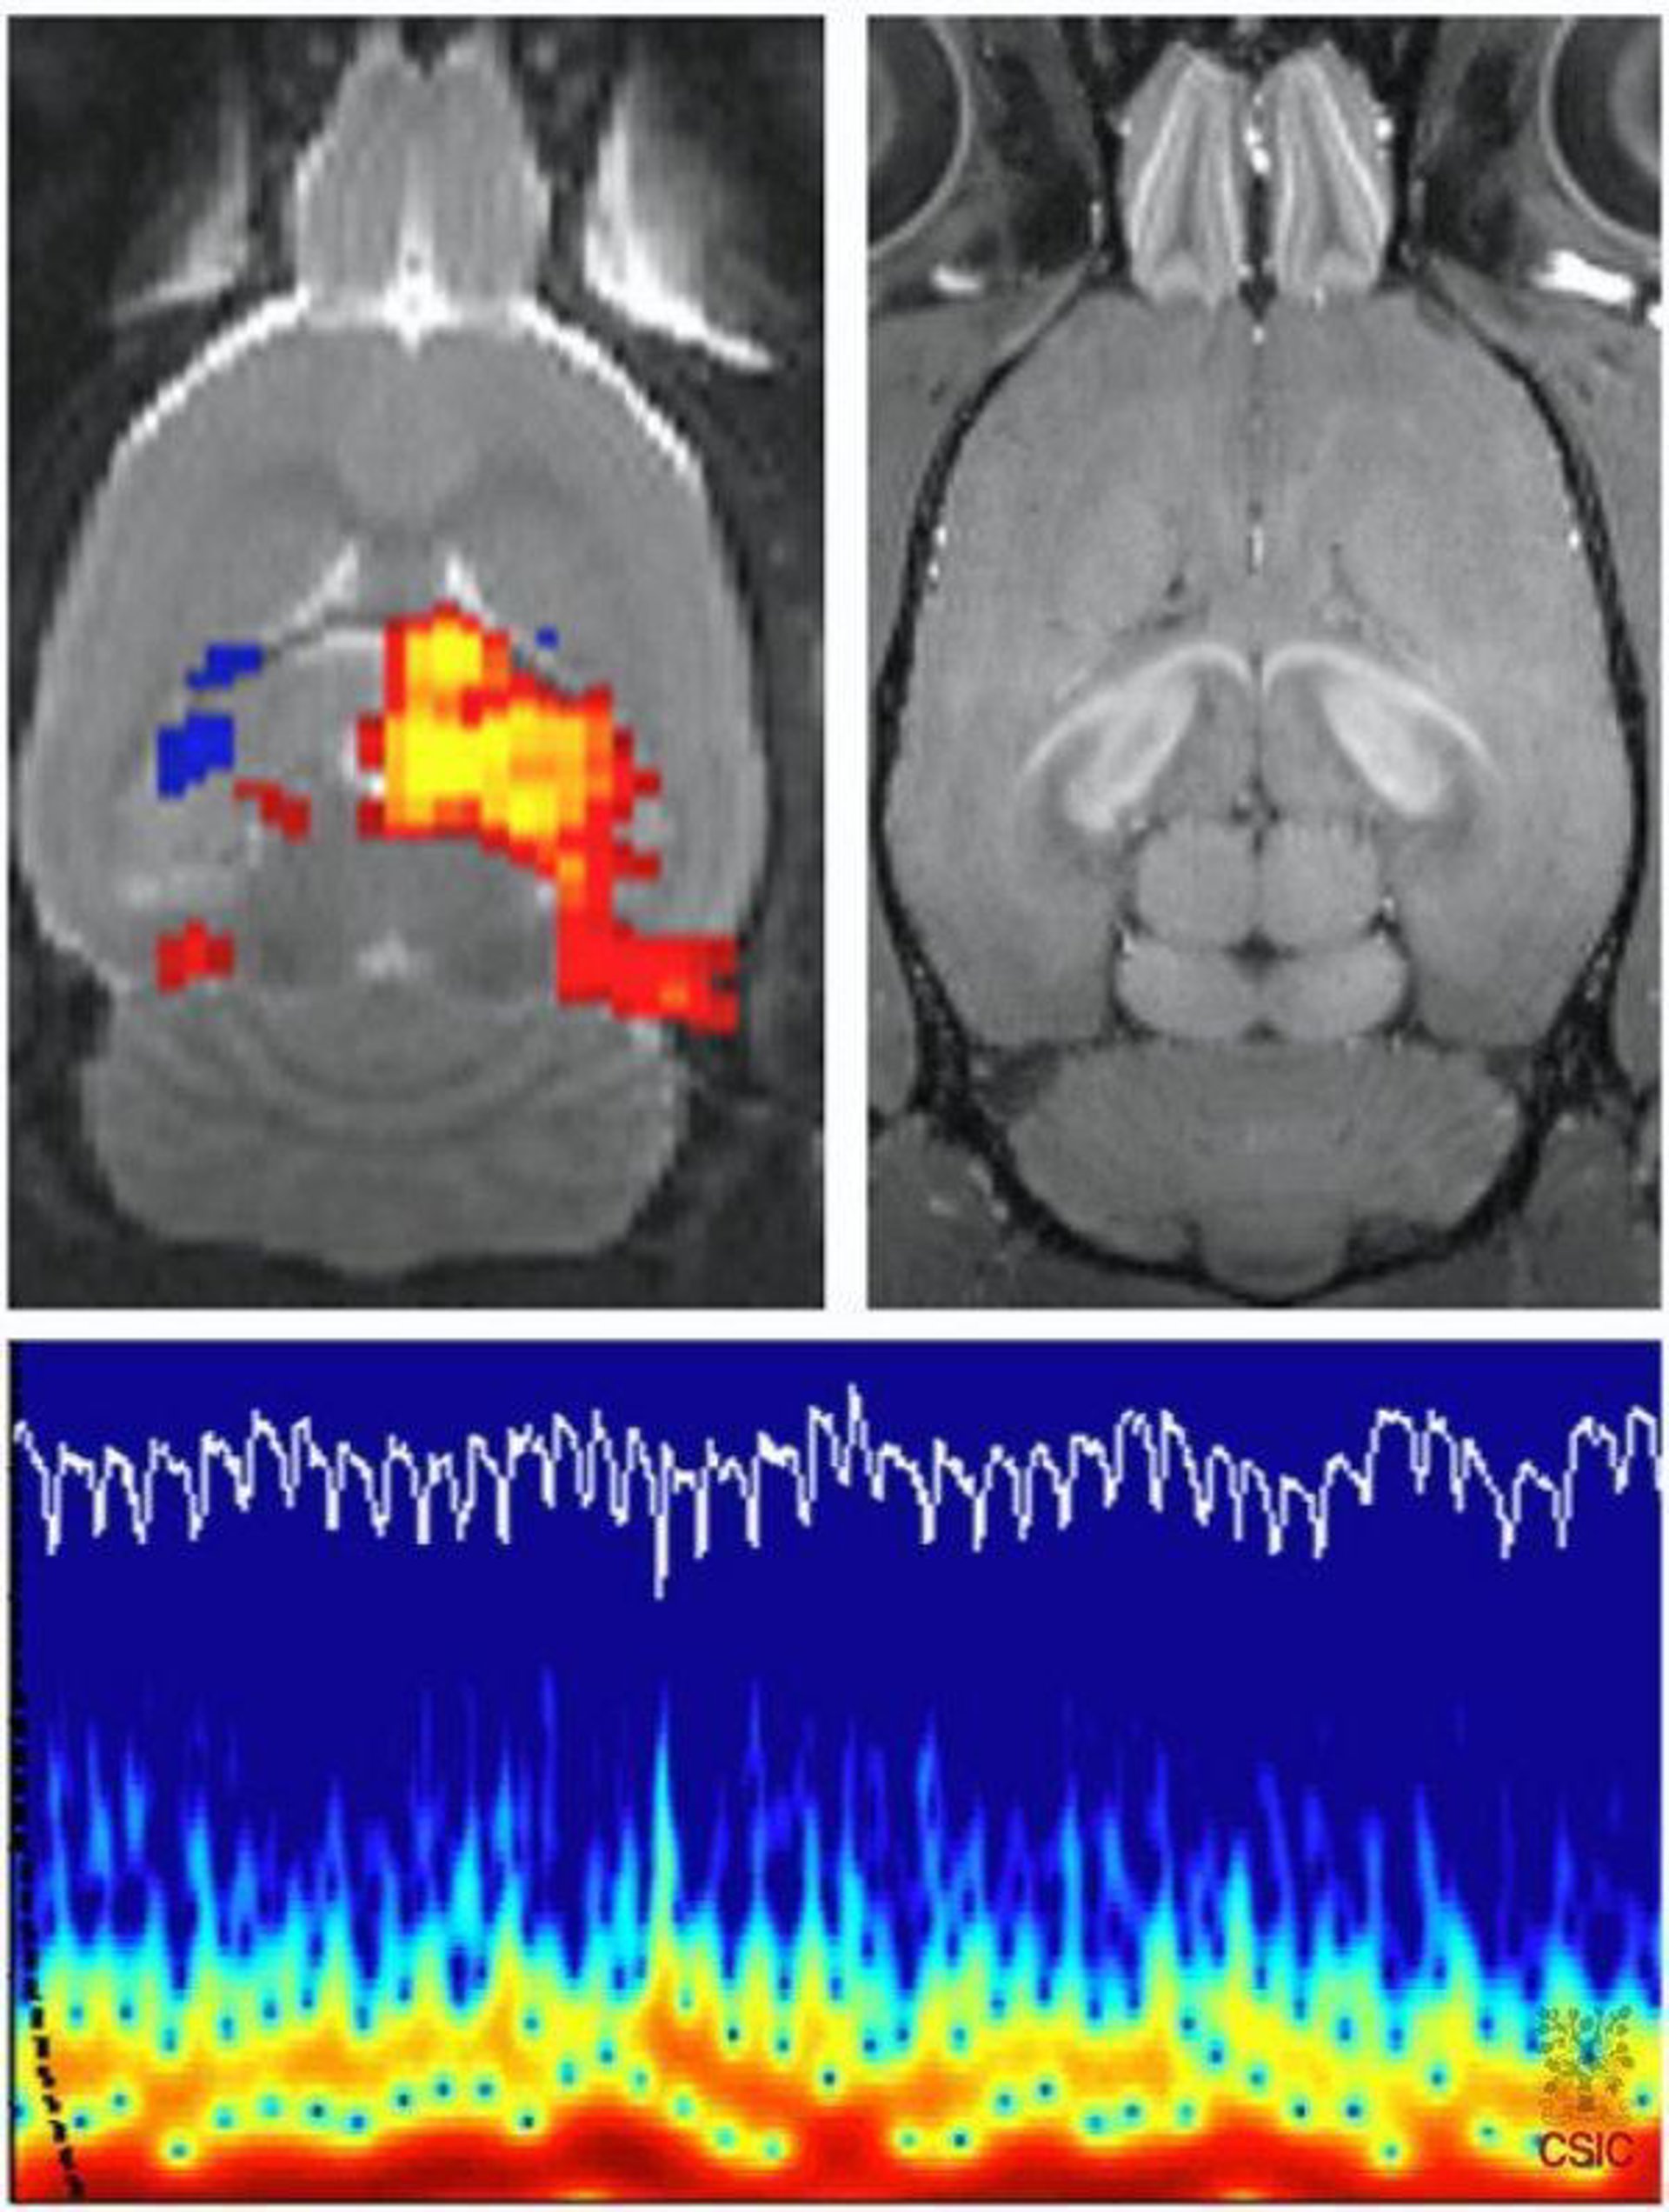

Investigadores del Medical Research Council de Reino Unido han conseguido establecer comunicación con un hombre que permanecía inconsciente desde hace cinco años estudiando los cambios de su actividad cerebral mediante el uso de imágenes por resonancia magnética funcional, según explican en un artículo publicado en el 'New England Journal of Medicine'.

Esta herramienta de investigación permite descifrar las respuestas del cerebro de personas sanas con total precisión, pero nunca antes se había probado su uso en pacientes con problemas de habla o movilidad.

Sin embargo, este paciente de 29 años, que sufría una grave lesión cerebral desde que sufriera un accidente de tráfico en 2003, fue capaz de pensar respuestas afirmativas o negativas modificando intencionalmente su actividad cerebral, de ahí que los autores vean en este hallazgo un avance en el cuidado de los pacientes en estado vegetativo.

Tras detectar señales de conciencia, los médicos escanearon el cerebro del hombre mientras le pedían que dijera "sí" o "no" a preguntas como "¿su padre se llama Thomas?". Los resultados demostraron que mediante cambios en su actividad cerebral, el hombre comunicaba su respuesta.

Este paciente es uno de los 23 pacientes diagnosticados en estado vegetativo que fueron examinados con la resonancia magnética funcional, con la que consiguieron detectar indicios de conciencia en otros cuatro pacientes.